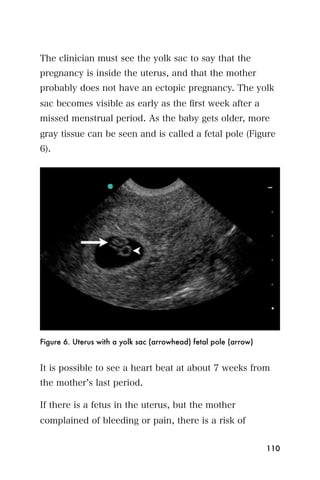

center that is the endometrium.

Figure 3. The bladder (*) and empty uterus (arrow)

An empty uterus may cause the clinician to worry about

an ectopic pregnancy. A ruptured ectopic pregnancy

blood may extend into the abdomen, so it is important

107

to look for blood within the abdomen as well as the

pelvis. The sonographer can begin imaging the area

between the liver and the kidney on the mother s right

side. This is the same window that is used to look for